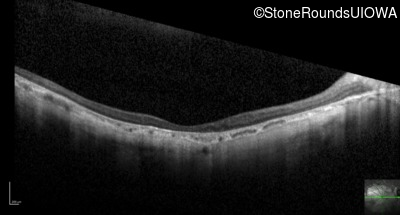

Optical Coherence Tomography - Left - 10/200 -3 sc

Exemplar / OCT Stack